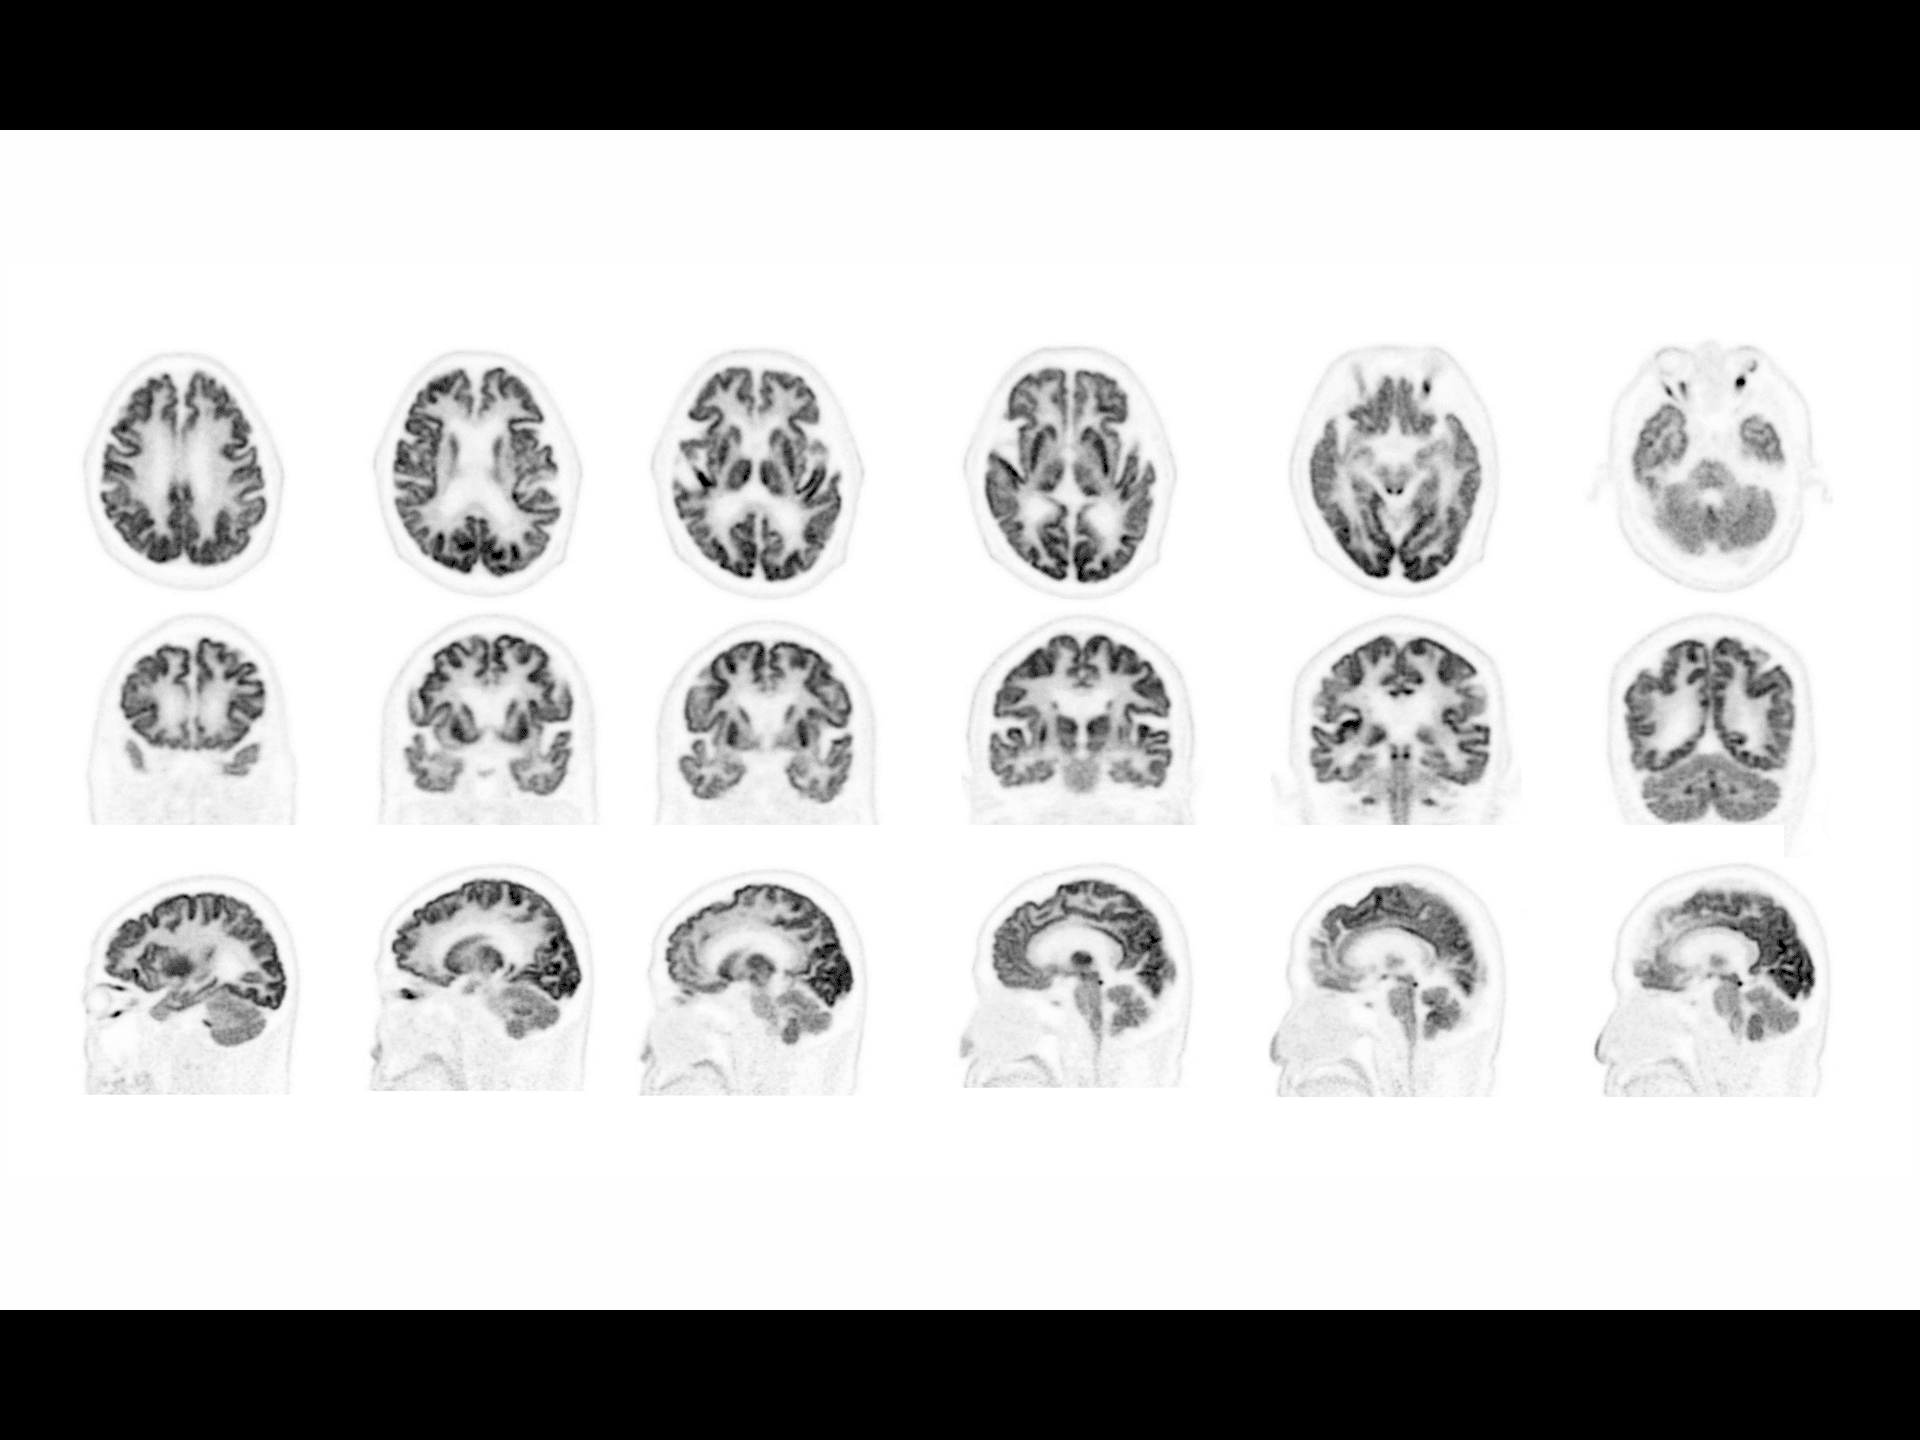

Imagine cerebrală PET/CT 18F-FDG de înaltă rezoluție

Scanare cerebrală clară și precisă, cu detalii fine vizibile pentru evaluări clinice avansate.